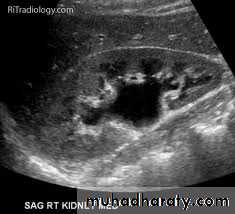

1-Dilatation of the P.C.S. appears as multilocular fluid collection within central echo complex.-With more severe distention, dilated calyces appear as Multiple cysts but communicating with each other unlike true cysts.

-Principal feature is dilatation of the pelvicalyceal system and ureter.

• The degree of dilatation depends on chronicity (long standing obstruction=more dilatation).

• The dilatation is down to the level of pathology